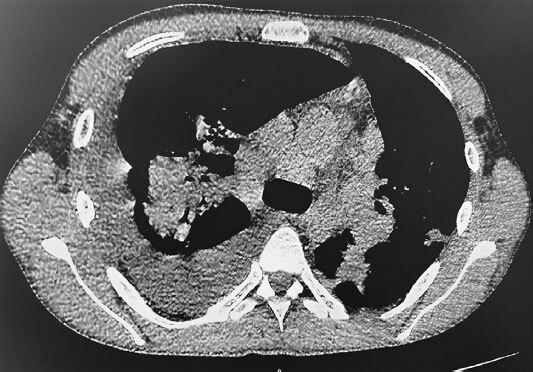

Рис. 2. КТ ОГП с внутривенным болюсным контрастированием от 01.06.2022 г.

01.06.2022 г. КТ ОГП с внутривенным болюсным контрастированием (контроль после пункции): по сравнению с результатами предыдущего КТ-исследования уменьшилось количество жидкости в правой плевральной полости (около 1300 мл). Корни легких расширены из-за множественных увеличенных лимфоузлов в них. Полисегментарно в паренхиме обоих легких сохраняются множественные массивные перибронхиальные участки консолидации с воздушной бронхографией. Визуализируются полости в S3 левого легкого – до 9 мм, в S9 – до 4 мм.

Заключение: уменьшилось количество жидкости в правой плевральной полости. Сохраняются признаки бронхиолита и перибронхиальной инфильтрации, мелкие полости в левом легком (буллы?). Распространенная лимфаденопатия может быть проявлением саркоидоза или лимфопролиферативного процесса.